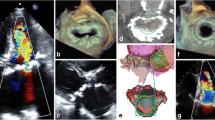

On M-mode echocardiography, MAC is seen as an echo-dense band near the mitral valve, usually beneath the posterior leaflet, anterior and parallel to the left ventricular free wall. On 2D echocardiogram (Fig. 2), it is seen as an irregular, echo-dense shell-like structure that produces acoustic shadowing [11, 38]. The calcific deposits are most often seen in the posterior part of the annulus, evenly distributed. When it occurs in the anterior region, it tends to be in the medial segment [39].

3D transesophageal echocardiography (Fig. 3) can be used to determine the effective orifice area of the mitral valve and mitral annular area by measuring the inner and outer mitral annulus and the posterior leaflet’s angle opening to calculate the reduction of the mitral valve area; thus, it can also be used to determine if the mitral valve should be approached in patients undergoing aortic valve surgery [40].

Two- and three-dimensional echocardiograms displaying caseous calcification of the mitral annulus. CCMA, caseous calcification of the mitral annulus. a 2D echo, b 3D echo (reproduced from Pala et al. [81])

CCMA is seen on transthoracic echocardiography as a round, echo-dense mass in the periannular region, usually close to the posterior leaflet, without acoustic shadowing artifacts with central areas of echolucencies resembling liquefaction [49], almost always presenting in the posterior leaflet, with some rare exceptions [50].

The diagnosis of CCMA by echocardiography can sometimes be difficult, especially in patients with poor acoustic windows. In such cases, cardiac CT can help in the diagnosis. CCMA appears in CT as an oval- or crescent-shaped hyperdense mass with a calcified rim [53].